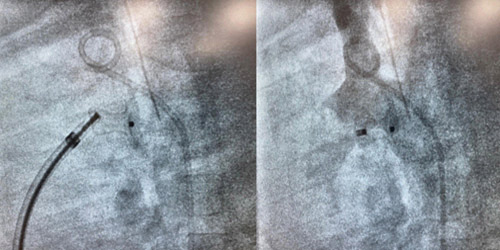

على إثر ذلك قرر الفريق الطبي الذي يضم استشاريين في عدد من التخصصات منها طب قلب الأطفال والتخدير والطوارئ والفريق التمريضي تجهيزه بشكل سريع وفوري لإنقاذ حياته، وذلك بإجراء قسطرة قلبية لإغلاق القناة الشريانية التي تسببت في تدفق الدم بالاتجاه الخاطئ.

وبفضل من الله تمكن الفريق من إجراء القسطرة عبر وريد الفخذ وإغلاق الوصلة بواسطة جهاز حديث وإعادة عضلة القلب لعملها الطبيعي، وتم بعدها مراقبة الطفل تحت الرعاية المكثفة بوحدة العناية المركزة الخاصة بالأطفال الخدج وحديثي الولادة NICU، وتولى استشاريو العناية المركزة بالوحدة رعاية الطفل حتى استقرت علاماته الحيوية وحالته الصحية تماماً وغادر المستشفى.